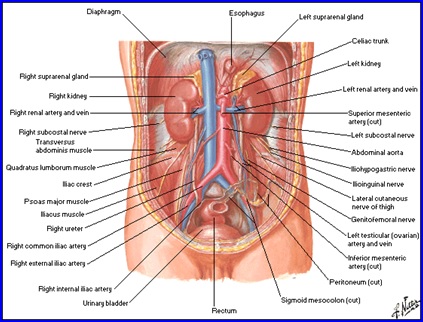

Aparatul Urinar

Glanda suprarenala

Anatomie

- glandă pereche situată la polul superior al rinichilor;

- formă piramidală în dreapta şi arcuată, semilunară în stânga;

- dimensiuni medii: 5/3/1 cm;

- greutatea ~ 5 g.

Rinichiul

Organ retroperitoneal, pereche şi simetric, cu formă asemănătoare bobului de fasole.

Dimensiuni şi greutate: depind de statura individului, vârstă, sex şi sunt în medie 12/6/3,5 cm; 140-170g.

Situaţie: de o parte şi alta a coloanei vertebrale, corespunzând vertebrelor T11-T12 superior şi L2-L3 inferior, de-a lungul marginii laterale a m. psoas. Prezenţa ficatului pe partea dreaptă face ca rinichiul drept să fie situat mai jos faţă de cel stâng.

Structură:

- Capsulă fibroasă; grăsime perirenală; fascia renală (Gerota); grăsime paranefretică.

- Sinus renal - elementele pediculului renal.

- Parenchim:

- corticala renală (1,2-1,5 cm grosime; conţine glomerulii renali şi segmente din tubii uriniferi);

- medulara (formată din 8-12 piramide renale).

Ureterul

- conduct intermediar între bazinet şi vezica urinară;

- 25-34 cm lungime, calibru inegal, cu strâmtori unde diametrul este de 2-4 mm şi “fuse” unde calibrul este de 5-10 mm;

- 3 stricturi anatomice:

- superioară - la nivelul joncţiunii pielo-ureterale;

- mijlocie - la incrucişarea cu vasele iliace;

- inferioară - la nivelul joncţiunii uretero-vezicale.

- traiect în ”S”

- după zonele pe care le străbate, se împarte în:

- Ureter abdominal

- Lombar

-Iliac - Ureter pelvin

- Parietal

- Vezical

- Ureter abdominal